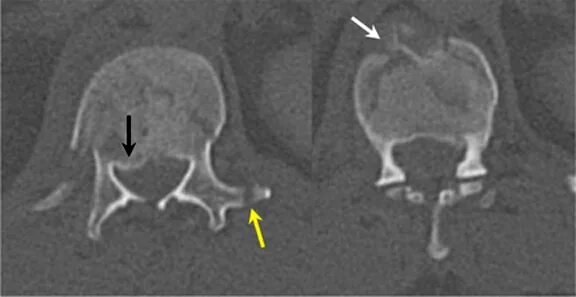

Перелом отростка l2